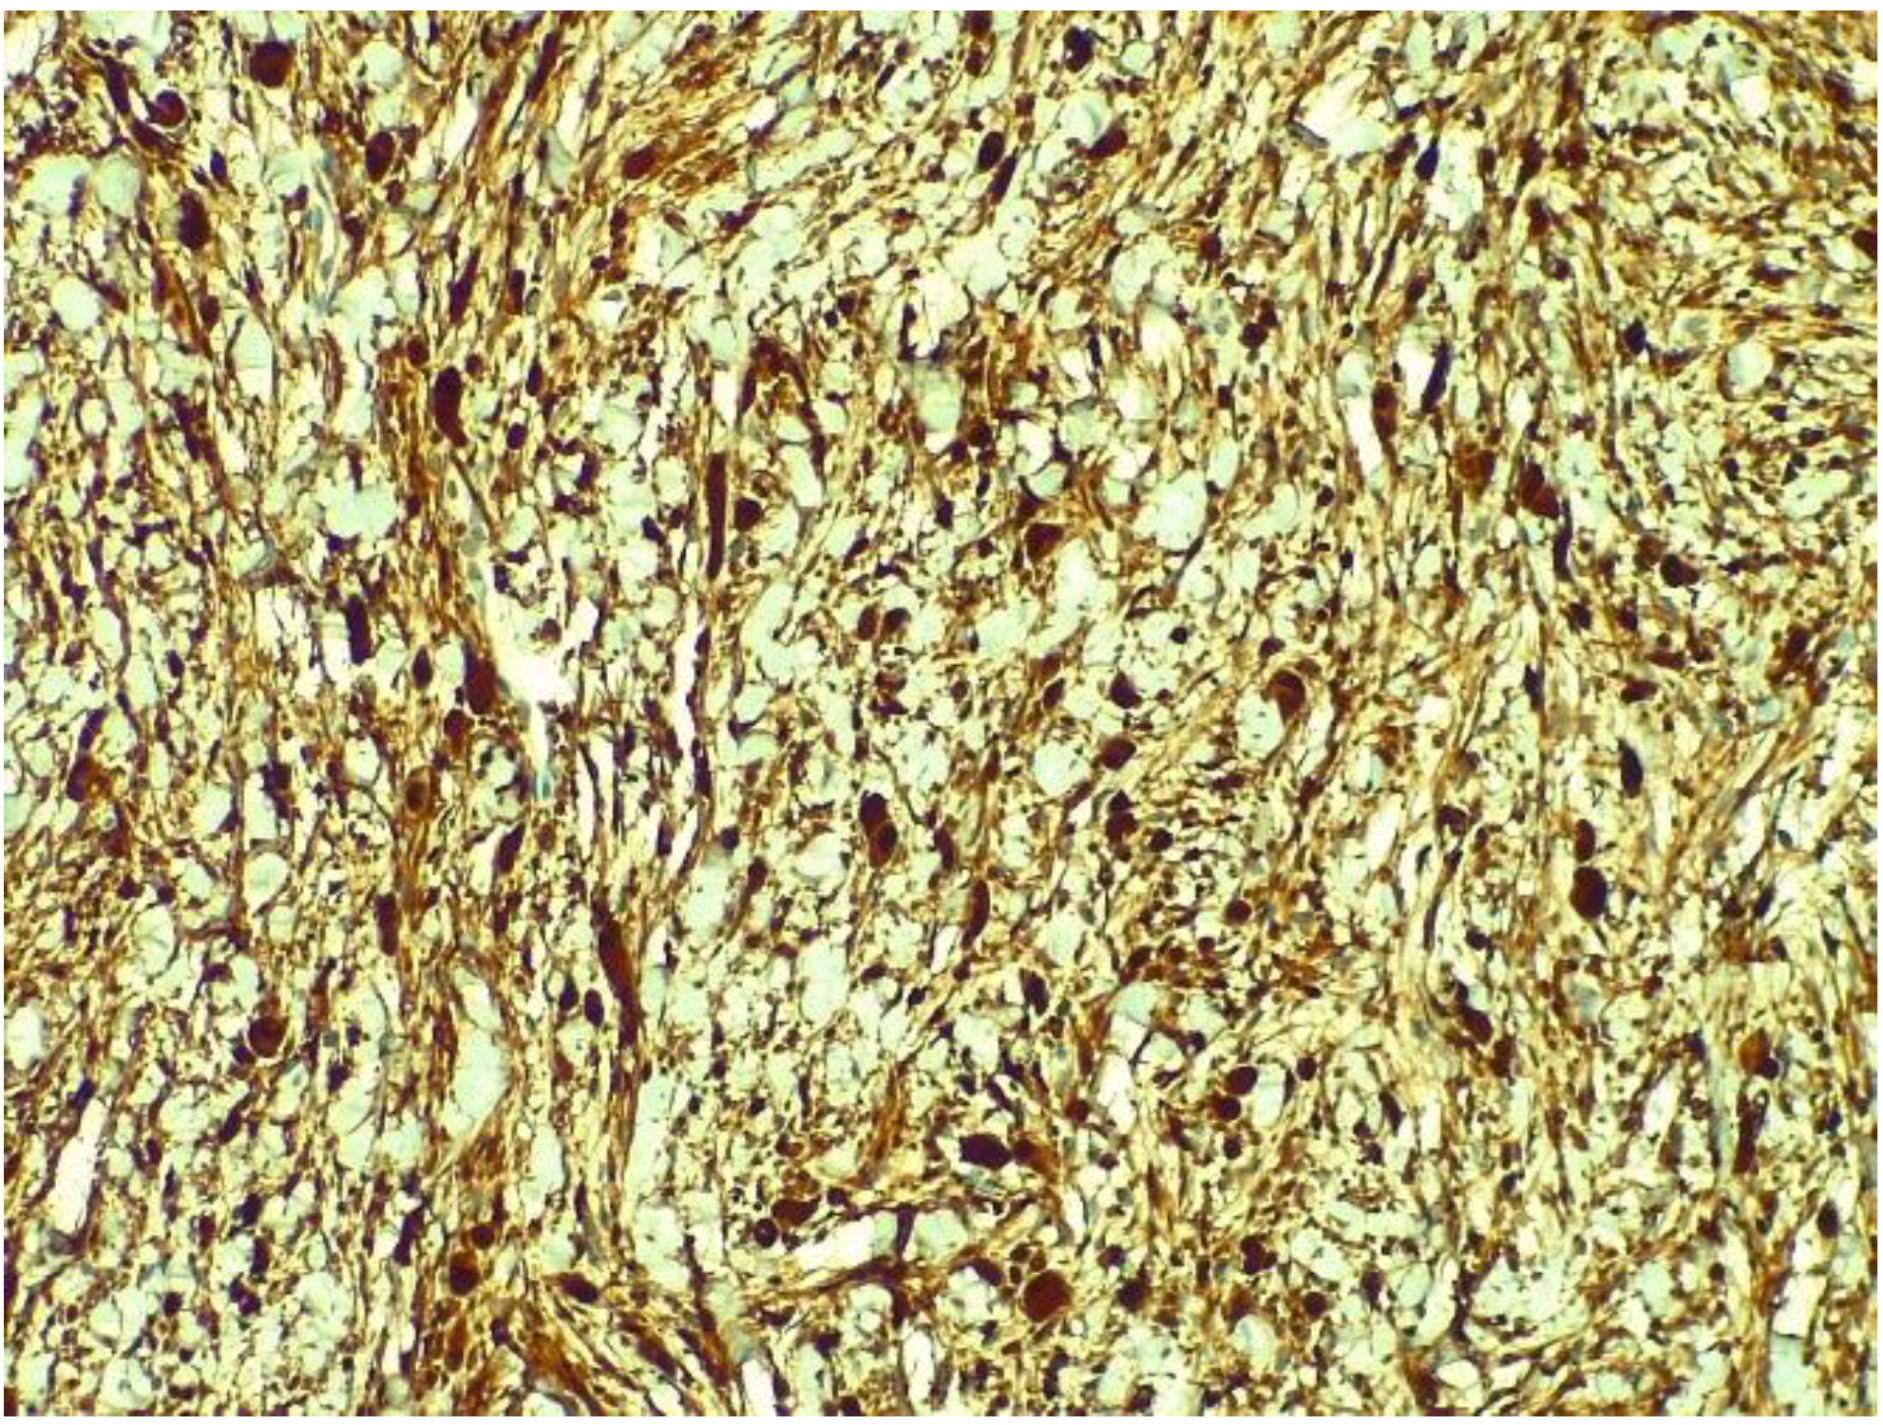

2. Case Report